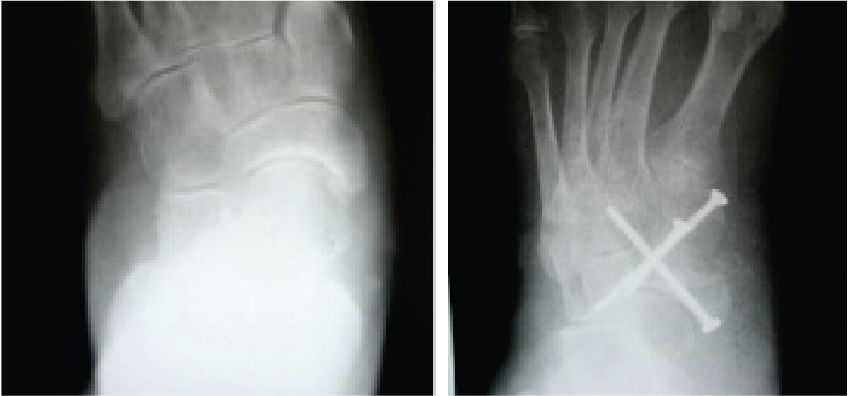

Patients with stage 2 PTTD present with a variety of deformities depending on planal dominance of the deformity. In patients with an unstable naviculocuneiform joint, one may note a sagittal plane collapse with a medial column sag demonstrating a naviculocuneiform fault radiographically. In transverse planal dominant deformities, one will see the too many toes sign with abduction of the midfoot and forefoot. The frontal plane deformities have a moderate heel valgus presentation with a forefoot supinatus or varus condition. The inability to perform a single limb rise test without inversion of the heel is common for advanced deformities where the function of the posterior tibial tendon has been lost due to an attenuated or ruptured posterior tibial tendon.

Imaging of the foot and ankle includes standard weightbearing views as well as long leg axial images to properly assess the foot to leg position. One may obtain advanced imaging with computed tomography (CT) or magnetic resonance imaging (MRI) if there is concern for additional deformities or to assess joint arthrosis. In certain cases, it may be helpful to obtain single-photon emission computed tomography (SPECT-CT) imaging to further pinpoint areas of increased bone activity.

The surgical management of adult-acquired flatfoot deformities due to PTTD involves many different procedures. The naviculocuneiform fusion helps reestablish needed stability to the medial column in patients who show clinical and radiographic evidence of medial column instability. One may perform the procedure as a stand-alone procedure in isolated cases but it commonly requires adjunctive lateral column procedures to realign the malaligned foot appropriately. Radiographic analysis of the medial column stabilization procedures with or without a calcaneal osteotomy has shown marked improvement.9 With appropriate patient selection, proper surgical technique and a stable fixation construct, this technique should provide the patient and the surgeon with a successful outcome.